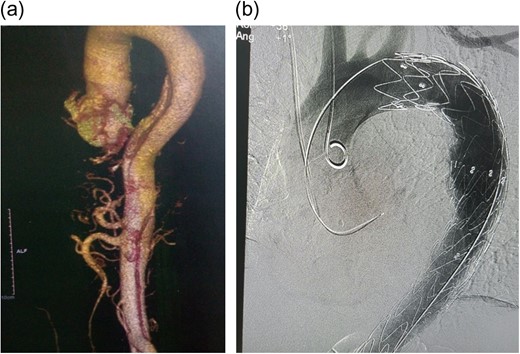

On examination, he had a blood pressure of 172/119 (right arm) and 137/92 (left arm). The rest of the cardiac examination was unremarkable. He had a full complement of pulses with no bruits or murmurs. High-sensitivity Troponin T was elevated (19.29 ng/ml), but not rising. An electrocardiogram (ECG) and a transthoracic 2D-echocardiogram showed left ventricular hypertrophy and no wall motion abnormalities. A computed tomography aortogram (CTA) was done showing an aortic dissection involving the descending aorta extending to the left common iliac, with iliac, superior mesenteric and both renal arteries arising from true lumen (Fig. 1a). He was admitted to the intensive care unit and started on morphine and labetalol infusion at 2 mg/h.

(a) CT Aortogram showing the dissection, 3D reconstruction; (b) immediate post-TEVAR showing contrast only in true lumen.

The patient was selected for TEVAR according to Cooper's [5] proposed algorithm and the decision reinforced by the history of non-compliance to medical therapy. A Valiant Captiva (Medtronic) 38 × 200 mm stent was deployed through the right femoral artery into the aorta, landing proximally just distal to the left subclavian artery and distally just distal to the celiac artery with an overlap of 110 mm and effective occlusion of the false lumen (Fig. 1b). Of note, 12 h post-TEVAR however; the patient started complaining of colicky, non-specific abdominal pains; associated with a leukocytosis, decreased platelet counts, the absence of fever and rising C-reactive protein (CRP) (Fig. 2). He was managed conservatively with non-steroidal anti-inflammatory agents (NSAIDs), antispasmodics and proton pump inhibitors (PPIs). Five days later, pains persisted, increasing in severity; with minimal relief with NSAIDs and antispasmodics. He also had thrombocytopenia, leukocytosis and elevated CRP. The abdomen was soft, surgical sites clean and bowel sounds present. An array of tests were done including procalcitonin (normal); blood cultures (negative); liver function tests (normal), serum amylase/lipase (normal); abdominal ultrasound (minimal gall bladder sludge); repeat ECGs (no changes); oesophagoscopy (normal) and magnetic resonance imaging of the thoracic and lumbar spine (normal). A repeat CTA showed the graft in place without endoleaks. In total, 16 days post procedure; he was started on intravenous steroids (for possible PIS) with dramatic clinical improvement and subsequently discharged home after 48 h in a stable condition.